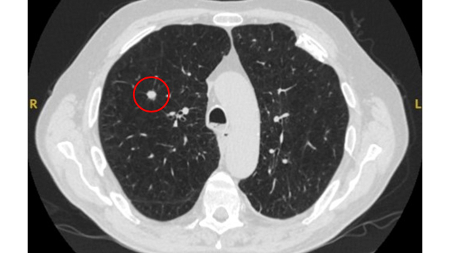

Solid nodules: volume doubling time of >600 days does not require follow-up, while a volume doubling time of <400 days, or clear growth defined as an increase in volume of 25% or more, suggests diagnostic investigations are required.[Figure caption and citation for the preceding image starts]: Computed tomography (CT) showing a right upper lobe spiculated solitary nodule within emphysema, in a current smoker with previous asbestos exposure. Note the visible pleural plaque on the left side. Resection histology revealed adenocarcinoma of the lungFrom the collection of Dr George Tsaknis, MD, PhD, FRCP(London), MRQA, MAcadMEd, PGCert; used with permission [Citation ends].

Ground-glass nodules: growth of 2 mm in maximum diameter should be considered potentially significant, while the development of a solid component suggests that further investigation and/or treatment should be considered.[Figure caption and citation for the preceding image starts]: Computed tomography (CT) showing a left upper lobe ground-glass nodule. This was eventually resected 2 years into surveillance because of growth and the histopathology confirmed adenocarcinoma of lung with mixed mucinous-lepidic patternFrom the collection of Dr George Tsaknis, MD, PhD, FRCP(London), MRQA, MAcadMEd, PGCert; used with permission [Citation ends].